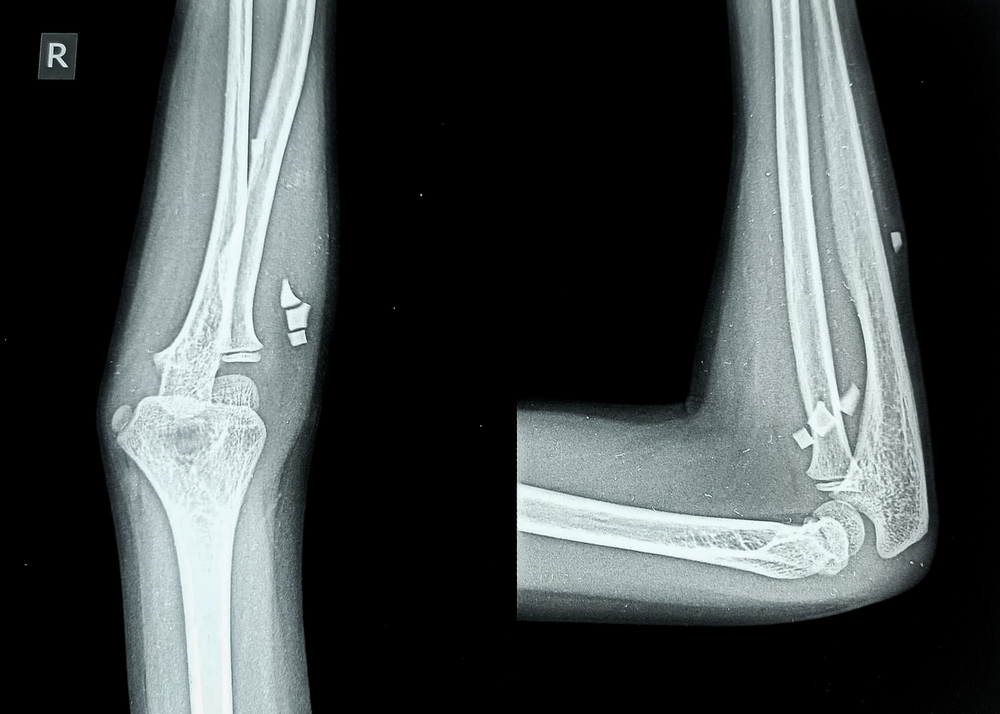

Стандарт диагностики — rg-снимок в двух проекциях: прямой (переднезадней) и боковой. Прямая показывает соотношение плечевой, локтевой и лучевой костей, ширину суставной щели, линии перелома; боковая — положение отломков, контуры локтевого отростка, «жировой» задний треугольник как признак выпота/гемартроза.

- Травма — тонкая линейная трещина, многооскольчатый перелом, смещение отломков; ступенчатость суставной поверхности головки лучевой; вывихи (чаще задние) с изменением оси предплечья; отрывные фрагменты в области прикрепления сухожилий; признаки гемартроза.